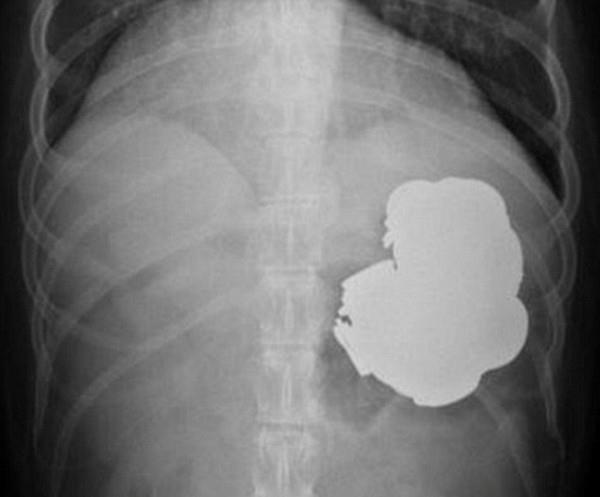

Depresyona girdiği için bu şekilde rahatladığını belirten adamın midesinde çekilen görüntüler ise şaşkınlık oluşturdu.

Doktorlar tam 240 işlem sonrasında metal objelerin bir kısmını çıkarmayı başardı. 34 yaşındaki adamın midesinden çivi, para, vida, pil ve mıknatıs gibi pek çok çeşitli metal çıkarıldı.